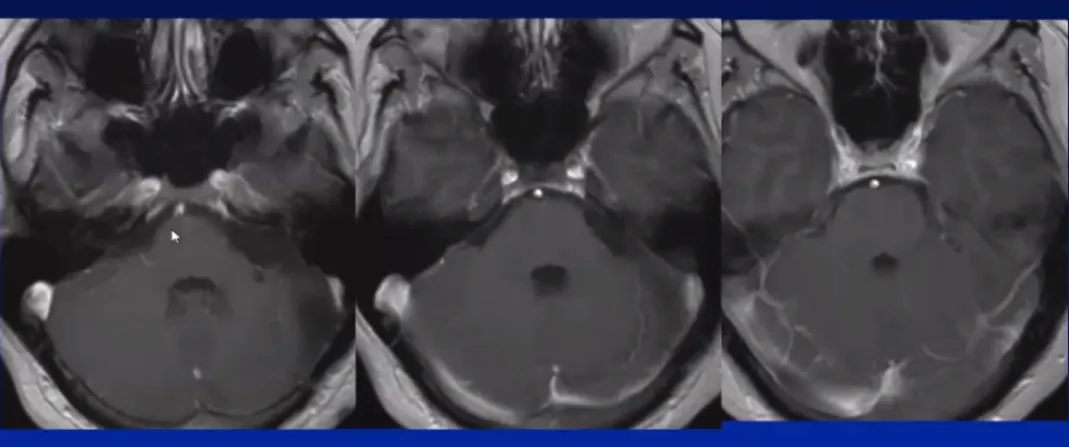

值得庆幸的是,卢卡最终在国际知名神经外科教授主刀下成功接受手术,肿瘤获完整切除,术后未出现面瘫等并发症。经过十年随访观察,患者已回归正常生活,病情保持稳定。

作为国际神经外科专家,巴特朗菲教授在听神经瘤治疗领域具有深厚造诣。在听神经瘤治疗过程中,巴特朗菲教授能够熟练运用神经导航、神经电生理监测、DTI及术中磁共振等先进设备,实施三维可视化精准显微手术,在彻底切除肿瘤病变的同时,有效保护听神经功能、面神经功能及周边神经功能区,从而保障患者术后生存质量。

不仅针对3cm以下的听神经瘤,对于具有极大挑战性的3cm以上大型听神经瘤,巴特朗菲教授同样能够在最大限度切除肿瘤的同时,显著保留神经功能。